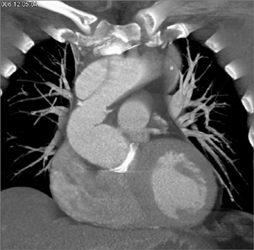

Type A Dissection